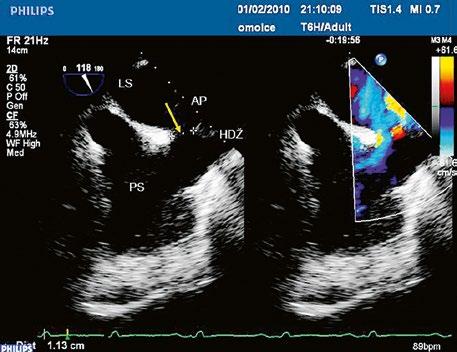

Obr. 45.5 TEE, longitudinální projekce, dva menší defekty typu sinus venosus inferior v dolní části síňového septa s levopravým zkratem označeny bílou šipkou, v místě vústění dolní duté žíly (DDŽ) do pravé síně (PS) LS – levá síň

Obr. 45.6 TEE, longitudinální projekce, menší defekt typu sinus venosus inferior (12 mm) označen křížky. (Stejná pacientka jako na obrázku 45.7.)

DDŽ – dolní dutá žíla, LS – levá síň, PS – pravá síň

Obr. 45.7 TEE longitudinální projekce, defekt typu sinus venosus inferior s menším levopravým zkratem v barevném dopplerovském mapování (stejná pacientka jako na obrázku 45.6)

z Defekt síňového septa typu sinus venosus superior: 9 %, v místě vústění horní duté žíly (HDŽ), která na defekt nasedá, téměř vždy je spojen s parciálním anomálním návratem pravostranných plicních žil do HDŽ nebo do pravé síně (kap. 45.18 Anomální návrat plicních žil (Obr. 45.3, Obr. 45.4, Video 45.3, Video 45.4).

z Defekt síňového septa typu sinus venosus inferior: 1 %, v místě vústění dolní duté žíly, může být sdružen s parciálním anomálním návratem plic